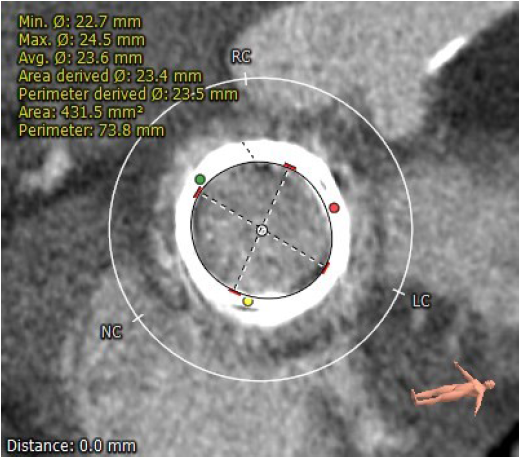

生物瓣瓣环内径23.5mm

生物瓣瓣环外径29.5mm

生物瓣环周围无明显钙化

生物瓣瓣架高度16.1mm